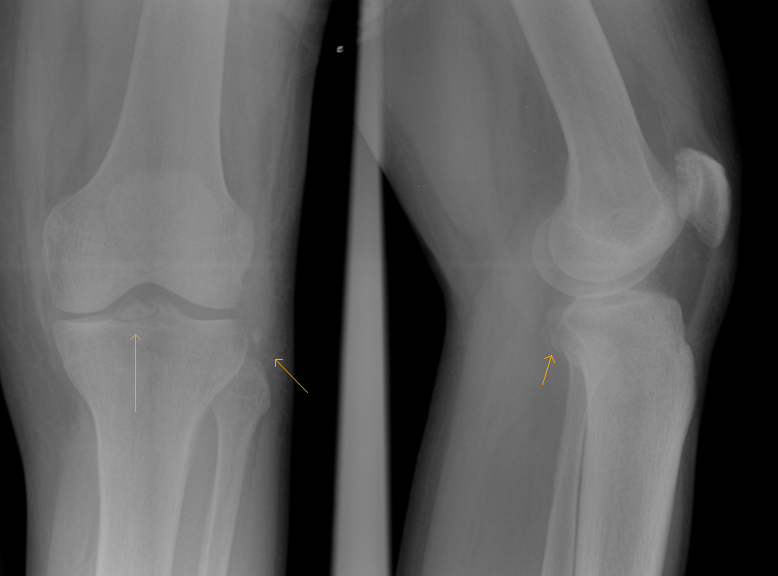

Avulsion fracture (small) of the lateral surface of the lateral tibial condyle. A segond fracture is an avulsion fracture located in the lateral aspect of the tibial plateau of the segond fracture:

A small avulsion that reflects major ligamentous damage. Imaging findings and clinical significance. Reverse segond fracture, as its name suggests.

Imaging findings and clinical significance. Nlm pubmed google websites google images quackwatch drugstore.com. Segond fracture is an avulsion fracture of the knee that involves the lateral aspect of the tibial plateau and is very frequently (~75% of cases) associated with disruption of the anterior cruciate ligament. Reverse segond fracture, as its name suggests. Segond fracture associated with increased probability of other soft tissue such as acl rupture; Search other sites for 'segond fracture'. All will feature in our upcoming emergency radiology course. Introduction the reverse segond fracture was rst reported by hall. A segond fracture is an avulsion of the lateral capsular ligament. Avulsion fracture (small) of the lateral surface of the lateral tibial condyle. The segond fracture of the proximal tibia: Segond fracture is typically the result of abnormal varus, or bowing, stress to the knee, combined with internal rotation of the tibia. It is frequently a varus stress that leads to a lateral collateral complex injury. The segond fracture is a type of avulsion fracture (soft tissue structures tearing off bits of their combined acl reconstruction and segond fracture fixation fails to abolish anterolateral rotatory. Segond fracture = avulsion of the anterolateral aspect of the lateral tibial plateau. Paul ferdinand segond was a french surgeon who not only was a knee specialist but also perfected the vaginal hysterectomy. ✪ fractures associated with acl injury: